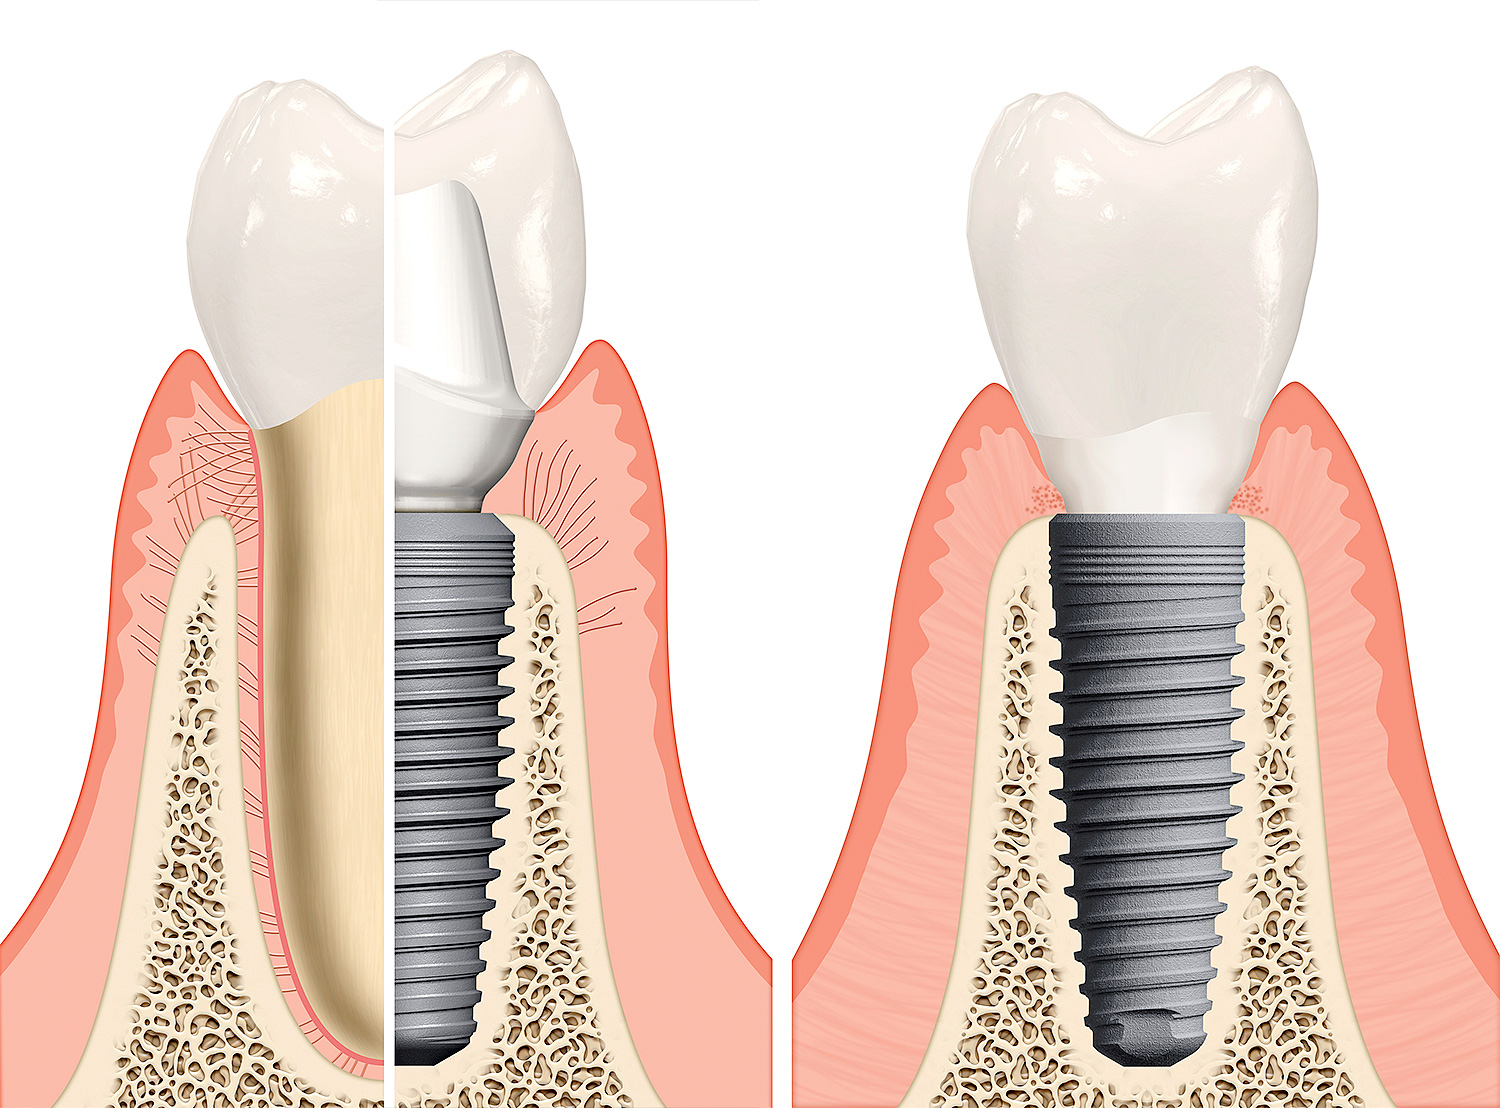

Dantų implantavimas su viso gyvenimo dantų implantų garantija

Dirbame su kelių gamintojų dantų implantais, jų tarpe, – su ypatingai aukštos kokybės, visame pasaulyje žinomais švediškais implantais, įvairiais jų priedais ir unikaliomis patentuotomis implantavimo metodikomis. Šio ženklo dantų implantų gamintojas, – kartu ir jų išradėjas, – nuolat patentuoja ir tobulina tiek pačius švediškus dantų implantus, tiek unikalias dantų implantavimo metodikas. Visi švediškų dantų implantų kūrėjų išradimai tuoj pat sėkmingai pritaikomi „Angitia“ klinikos pacientams.

Visiems švediškų dantų implantams bei sistemoms, nepriklausomai nuo implantavimo metodikos, suteikiama viso paciento gyvenimo garantija, galiojanti 70-yje pasaulio šalių. Kiekvienoje šalyje dažniausiai yra daugiau, nei po vieną odontologijos kliniką, dirbančią su to paties ženklo švediškais dantų implantais. Tad kur bekeliautumėte, švediškų dantų implantų servisas, galima sakyti, yra visada šalia Jūsų.

Unikalios dantų karūnėlės, arba vainikėliai – 3-jų dalių vainikėlio iš cirkonio monoblokas. Vainikėlio bazinė dalis, apdaila ir atrama – viskas vienoje nedalomoje monolito detalėje, kuri yra ir visada bus patvaresnė, nei sujungta iš atskirų kelių dalių. Dar tobulesnio danties vainikėlio ir atramos sprendimo būdo kol kas odontologija nežino.

Specialiosios dantų implantų atramos, – unikalus sprendimas, apsaugantis dantenas nuo jų sudirginimo danties primatavimo ir protezavimo ant implanto metu. Pritaikius šią atramų sistemą, lengviau ir greičiau sugyja dantenos, nes visų implantavimo etapų metu dirbama ant šios atramos kaklelio. Pasaulio odontologams ši sistema buvo pristatyta 2016 m. birželio mėn., ir po kelių dienų panaudota „Angitia“ klinikos pacientams.